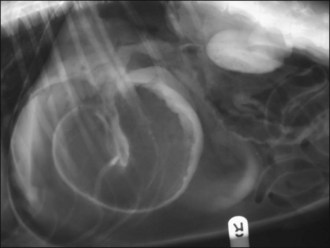

Abdominal radiography reveals convoluted loops of tubular fluid opacity in the caudal abdomen with dorsal displacement of the descending colon (Figure 29.9), and ultrasonography shows enlarged uterine horns distended with hypoechoic fluid (Figure 29.10).

Figure 29.9 Right lateral abdominal radiograph in a dog with pyometra. Convoluted loops of tubular fluid opacity are visible in the caudal abdomen.